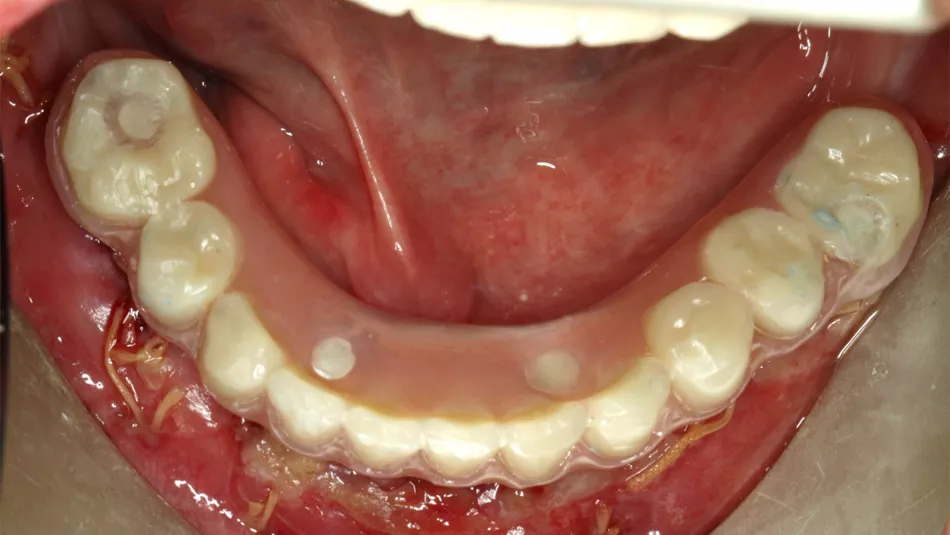

Treatment: The treatment plan was performed with a computer software and included the use of four straight Straumann® BLT implants in the lower jaw. Following local anesthesia, and a mid-crestal incision was done. The flap was raised with minimal trauma, the inflamed tissue was removed, and the bone level was adjusted. The implant bed was prepared with the help of a guide and the manufacturer’s protocol was followed. Two implants were placed behind the mental foramina and two in front of it, providing an ideal spread. The placement of implants in resorbed bone led to the need of bone augmentation around the exposed surfaces of the implant. After the surgical procedures, the bite registration was performed, and the impression was sent to the laboratory. Couple of hours later, the temporary prosthesis was placed on the patient and the occlusion was checked.

Treatment outcome: The patient’s expectations were fulfilled as he was able to have a fixed immediate restoration, that allowed him to go back home the same day of the surgery and recover the chewing function.